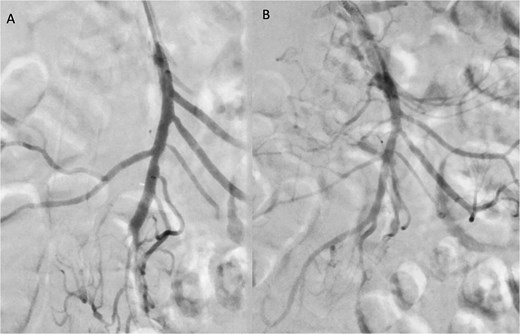

A 76-year-old female patient with a medical history of diabetes mellitus and cholecystectomy presented to the emergency department with a 7-month history of postprandial abdominal pain, food fear, and weight loss (25–30 kg). Over the past 3 days she referred symptom worsening to constant pain. On the physical examination, the abdomen was tender to palpation. Laboratory results revealed leukocytosis (13.700/μl), high C-reactive protein (23 mg/dl) and lactate 0.7 mmol/L. A previously performed computed tomography angiography (CTA) in context of a lithiasic cholecystitis revealed celiac trunk occlusion and pre-occlusive stenosis of the SMA ostium but the patient was not referred for a vascular surgery consultation. A CTA scan obtained in the emergency department revealed thrombotic occlusion of the SMA origin associated with distal embolization (Fig. 1A–C). In this context, the diagnosis of acute-on-chronic mesenteric ischemia was assumed, and the patient was proposed for urgent endovascular revascularization. A 7F (French) sheath was placed via percutaneous access in the left brachial artery, and SMA catheterization was performed using a triaxial system (sheath, MP catheter and Progreat® catheter). Diagnostic angiography confirmed the CT findings (Fig. 2A). Catheter-directed thrombolysis was first performed with a 5 ml bolus of alteplase, followed by percutaneous thrombectomy using the Penumbra® system (Fig. 2B), with retrieval of fresh thrombus (Fig. 3). Primary stenting of the SMA ostium was also performed using an Advanta® 6 × 39 mm stent with proximal flair, with an excellent imagological result (Fig. 4A and B). The postoperative course was uneventful, with significant improvement of symptoms and clinical status. A CTA prior to discharge revealed a patent stent with proper placement and no evidence of residual thrombus (Fig. 5A and B). The patient was discharged on the seventh postoperative day with apixaban 5 mg twice daily. Follow-up of the patient at 6 months revealed that the stent remained patent, with no reported abdominal complaints. The patient gained 15 kg at this point of follow-up.

Angiographic images before (A) and after (B) primary stenting of SMA ostium using a 6 × 39 mm Advanta® stent with proximal flare.